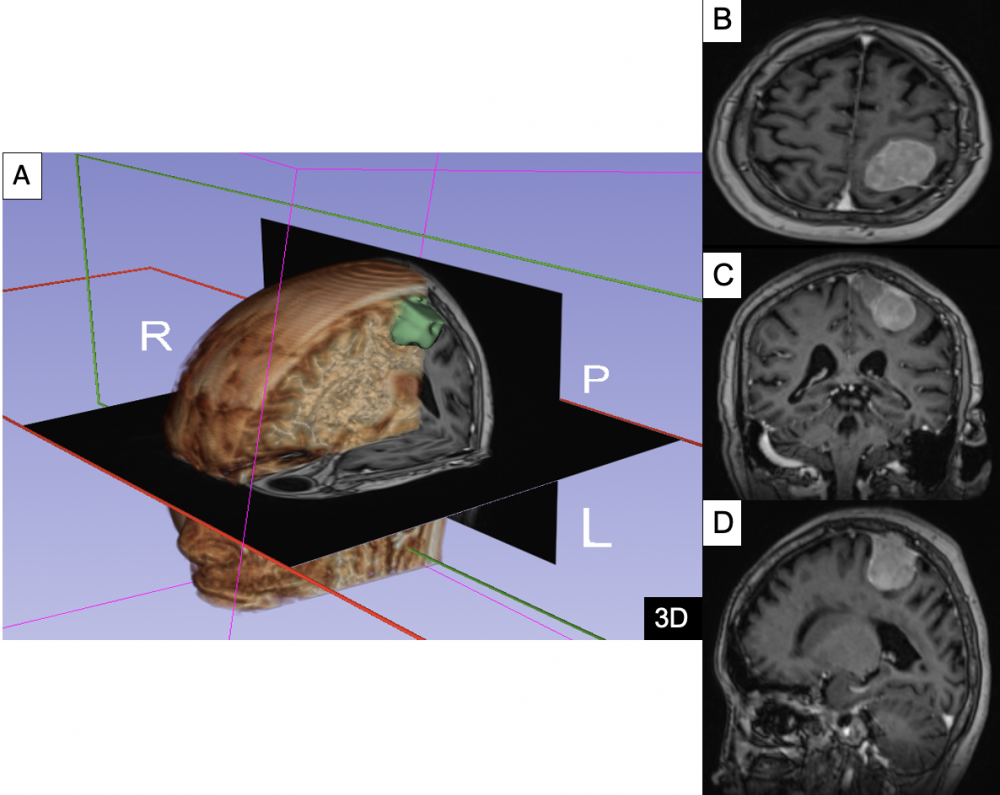

Toàn bộ dữ liệu hình ảnh (CT, MRI) của bệnh nhân được xử lý bằng phần mềm 3D Slicer để xây dựng mô hình không gian 3 chiều.

Hình 1. Lập kế hoạch 3D trước mổ u màng não đỉnh trái bằng phần mềm 3D slicer